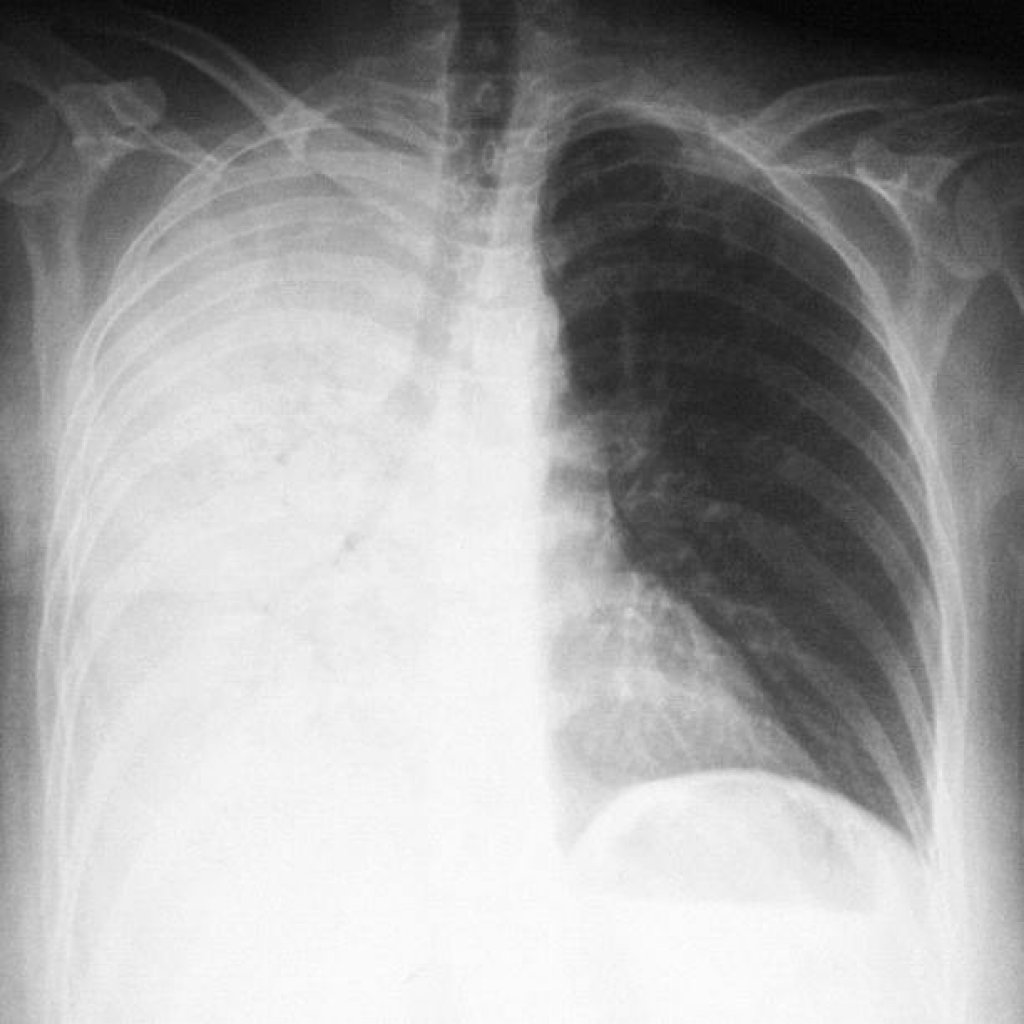

Если есть проблемы с дыханием, возможно это пневмония, которая отдает в нижнюю часть спины

Острые боли в пояснице у женщины могут спровоцировать и совсем другие заболевания:

- Пневмония. Если в воспалительный процесс включается поражение плевры, боль отдает даже в поясницу, конечности, другие части тела. Боль становится острой, усиливающейся при вдохе, простреливающей. Может сопровождаться кашлем, температурой, трудностями с дыханием, отдает под лопатки и в область грудины. У пациента наблюдается тяжелое, хриплое дыхание.